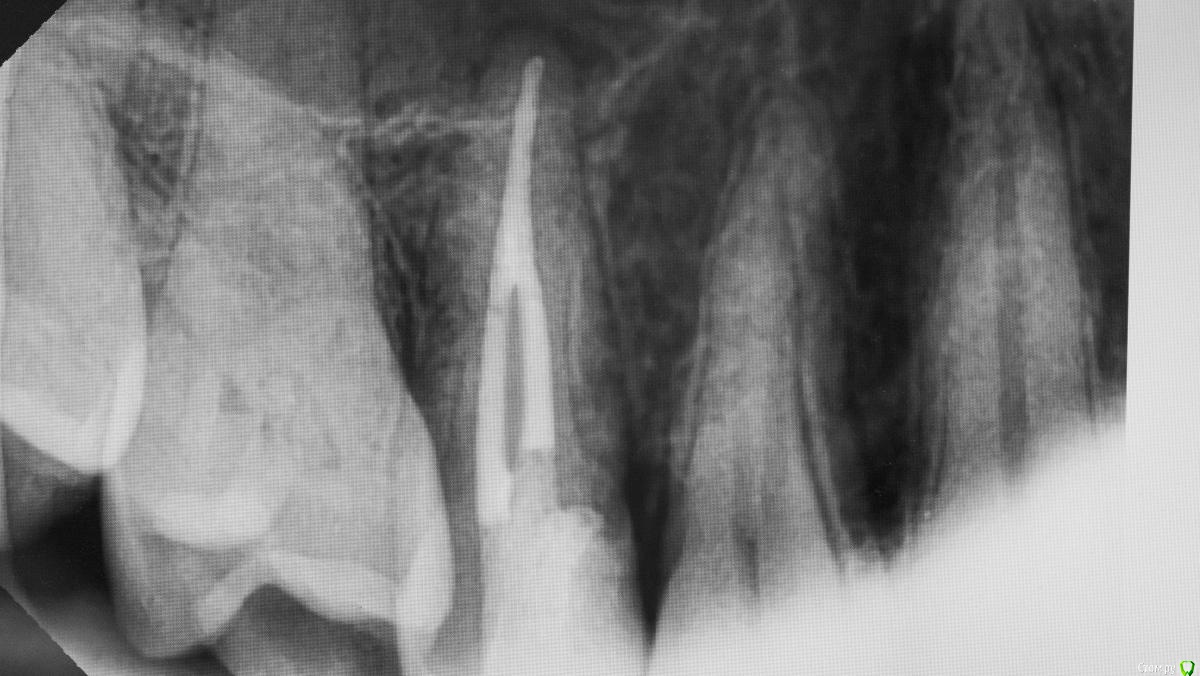

Kolchanov Опубликовано 19 апреля, 2018 Поделиться Опубликовано 19 апреля, 2018 Каплан, а есть какой-нибудь кейс с реальным поддесневиком. Где матрицу по полчаса вкорячиваешь. А то я все понимаю, эргономика, туда-сюда, но меня не покидает ощущение, что, когда попадается реально сложный случай, то микроскоп со вздохом отодвигается и начинается реальная жизнь стоматолога 7 Ссылка на комментарий

Kolchanov Опубликовано 19 апреля, 2018 Поделиться Опубликовано 19 апреля, 2018 Тут на фейсбуке какой-то доктор, кажется из лекторов, показывает случай с "поддесневым" разрушением, как он его назвал. И говорит, что чтобы не изменять профиль матрицы надо тефлоном подоткнуть вместо клина. А я смотрю и глаза протираю. Не вижу поддесневика. Коффер инвертирован, все путем. Ну, надо видеть конечно. Но я к чему, неужели только у меня что ни день то кариес-поддесневик? Ссылка на комментарий

Паращук Роман Опубликовано 20 апреля, 2018 Поделиться Опубликовано 20 апреля, 2018 Поддесневиков каждая третья полость. Далее или удлиняем и с помощью молотка и чей-то матери тулим матрицу,или удаляем. Ссылка на комментарий

Л Ю С Я Опубликовано 20 апреля, 2018 Поделиться Опубликовано 20 апреля, 2018 Матрицу тоже можно глубоко засунуть, не проблема, поджать фумкой, клином. Но контакта плотного получить, вот это реальная проблема 1 Ссылка на комментарий